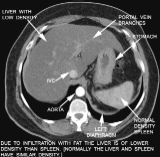

この衝撃的な出来事からおよそ4年後の昨年6月のこと。健康診断の結果を見て再び愕然とする。診断結果に見慣れないコメントが載せられている。「わずかに脂肪肝が認められます」と。「脂肪肝ってなんだ?」

これまでの診断結果では、ずっと血中の中性脂肪値は高かったのだが、特に気にもとめなかった。高かったとはいえ一応、基準値内だったからだ。しかし、今回はその中性脂肪値も基準の枠を大幅に越え、しかも「脂肪肝が認められる」とは。

「もはや、この状態を放置しておくことはできまい。何か手を打たねば。」そう考えた私は、まず情報収集から始めた。その結果、重大な事実が判明した。なんと、中性脂肪が増え脂肪肝になると疲れやすい、だるさが抜けない、いつも眠いなどの症状がでるとのこと。

これはまさに、これまでの私の体調を物語っているではないか! 「そうだったのか。もっと早く教えてほしかった。毎日のように『なんかテキナイのー』と言っていたのは中性脂肪のせいだったに違いない。」 中性脂肪値が高いことの弊害はそれだけではなかった。なんと、動脈硬化を引き起こすことにもなるらしい。